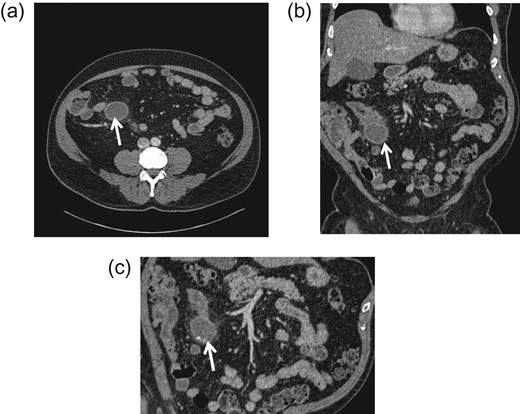

CT abdomen and pelvis (a) transverse; (b) frontal (coronal); and (c) sagittal view. An arrow indicates a blind ending sac at mid-ileal loop.

The learning point of this clinical vignette is that Meckel's diverticulitis is often clinically indistinguishable from appendicitis especially in adult patients. Computed tomography (CT) has become an invaluable tool for the evaluation of abdominal pain. CT scanning is useful in demonstrating acutely inflamed diverticula, typically identified as a blind pouch off the distal small intestine and associated with bowel wall thickening and in detecting the presence of enterocolic and enterovesical fistulas.